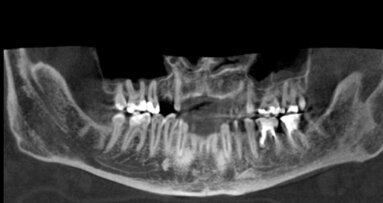

67-letnia pacjentka zgłosiła się do gabinetu stomatologicznego w celu konsultacji w sprawie leczenia implantologicznego. W wywiadzie zgłaszała pewne ...